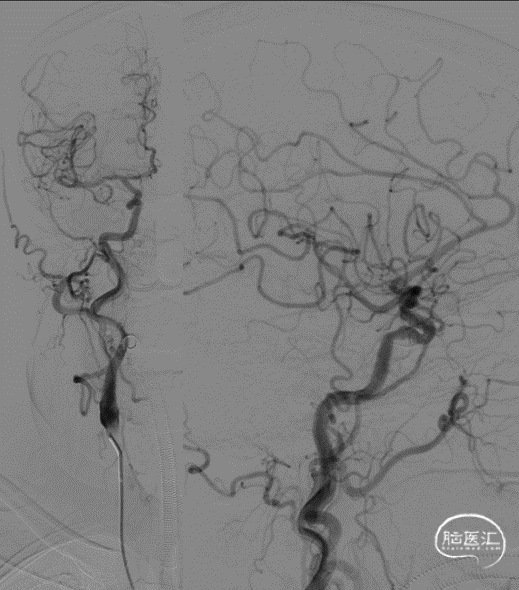

DSA(2022-01-19):

L-ICA

L-VA

R-ICA

复查DSA:左侧椎动脉V4段重度狭窄。